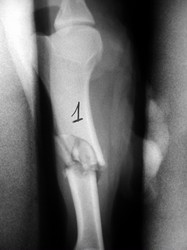

Fijación Externa

Fijación externa en IVOT

PRÁCTICAS CURSO DE FIJACIÓN EXTERNA PERFECCIONAMIENTO.

Húmero.